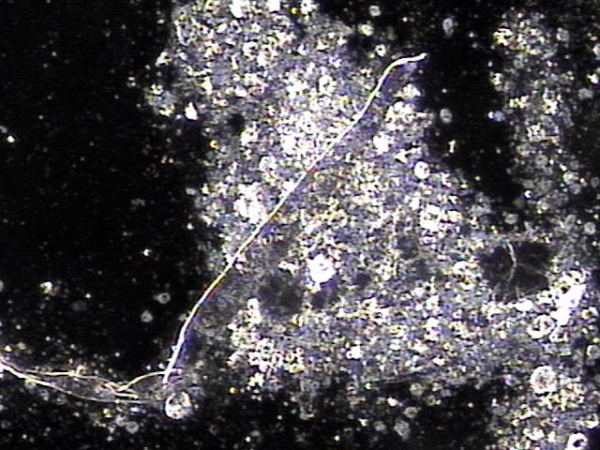

탈락된 상피세포로 좁아진 사정관과 전립선관 그리고 사정관 입구의 결석들이 배출시 손상된 조직 치료되고 전립선의 표적치료후 치료된 전립선과 사정관 결석과 염증세포 덩어리의 현미경학적 자료입니다.

This is a microscopic image showing treated prostatic and ejaculatory duct stones, along with clusters of inflammatory cells, after targeted therapy of the prostate. It illustrates the healing of tissues damaged during the expulsion of dislodged epithelial cells, which had narrowed the ejaculatory ducts, prostatic ducts, and ejaculatory duct openings.